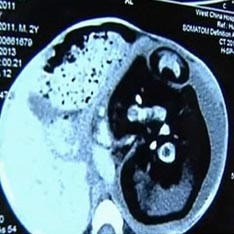

Chirurgové našli svého nenarozeného v žaludku dvouletého dítěte Siamské dvojče. S neobvyklým případem ve své praxi čelí lékaři z Číny. Poté, co lékaři vyšetřili dvouletý chlapec s obrovským břichem z vesnice Huashi, ukázalo se, že v něm byl jeho nenarozený dvojčata. Bylo rozhodnuto podstoupit nouzovou operaci, protože žaludek byl oteklý – neuvěřitelné velikosti, vnitřní orgány se začaly stahovat a – pro dítě bylo těžké dýchat, píše Daily Mail. Ukázalo se, že bratr, který byl v něm celou tu dobu, nebyl moc menší než chlapec sám. Jeho tělo nebylo dostatečně vyvinuté, ale páteř, končetiny a prsty na pažích a nohou jsou plně zformovány. Tenhle případ, jak vysvětlují lékaři, je jednou z odrůd Siamese dvojčata. Oni jsou narozeni, když oplodněné vejce není plně sdíleno. Jak však poznamenal novorozenec z mateřské školy Nemocnice Cleveland Dr. Jonathan Fanarof, v případě “těhotné” dítě, vejce nesdílel.

V celé historii medicíny existují stovky případů, kdy jeden embryí dvojčat „absorbuje“ jeho bratr a pokračuje vývoj v něm. Tento jev se vždy objevuje brzy. fáze těhotenství, a obvykle obě plody umírají v lůně matky. Stává se však, že porod je úspěšný a chycen embryo pasti nadále žije jako parazit s ním spojený velký bratr jakési pupeční šňůry. Nakonec on stává se tak velkým, že se začíná poškodit majiteli. V medicíně se tato anomálie nazývá fetus in fetu (embryo v embryu). Mimochodem, stejný případ byl zaznamenán před několika lety v Indii. Břicho 36letého Sanju Bhagata bylo natolik natolik, že vypadal jako žena, která se chystala porodí. Chirurgové si byli jisti, že má obrovský nádor, který stiskne membránu. Ale jaké bylo jejich překvapení, když z něj vyšel vytáhli lůno zmutovaného těla svého dvojče.